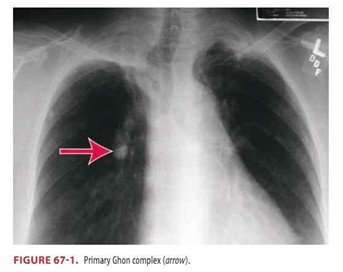

◎ 흉부X선 촬영 : 폐결핵을 진단하는 데 가장 일반적으로 사용되는 검사입니다.